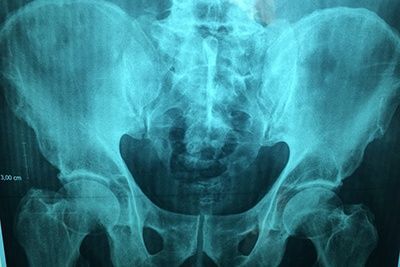

Таз представляет собой часть скелета, которая расположена в основании позвоночного столба. Он не только является опорой для внутренних органов, но и обеспечивает фиксацию к туловищу ног. Именно поэтому его здоровье играет немаловажную роль, а рентген костей таза является неотъемлемой составляющей диагностики при заболеваниях и травмах этой области.

Он является диагностическим высокоинформативным методом, позволяющим получить данные о состоянии костных структур и суставов таза, определить повреждения и патологии мягких тканей и внутренних органов. Рентгенографию широко применяют в поликлиниках, поэтому она является доступным методом, в том числе и в ценовом плане. Пройти рентген костей малого и большого таза можно в диагностическом центре многопрофильной клиники ЦЭЛТ. Мы располагаем современным оборудованием, а наши специалисты практикуют индивидуальный подход, что неизменно позволяет добиваться высокого качества рентгенографических снимков.

Что показывает рентген костей таза?

Расшифровка полученных результатов требует не только чётких снимков, но и соответствующих знаний у врача. Это обусловлено тем, что однотипные изменения имеют различную трактовку. Именно поэтому в процессе нужно учитывать анамнез и жалобы пациента: каждое заболевание или аномалия имеют определённые клинические проявления. Так:

- Заметные на снимке смещения в тазобедренном суставе сигнализируют о его вывихе;

- Аномалии строения головки кости бедра и вертлюжной впадины — признаки дисплазии;

- Сужение суставной щели и наличие остеофитов говорят о таком дегенеративно-дистрофическом заболевании, как остеоартроз;

- Затемнения — признак злокачественных новообразований, тени — метастатические очаги;

- Обломки костей подтверждают подозрения о переломе;

- Хорошо заметная регенерация костных структур является симптомом асептического некроза.